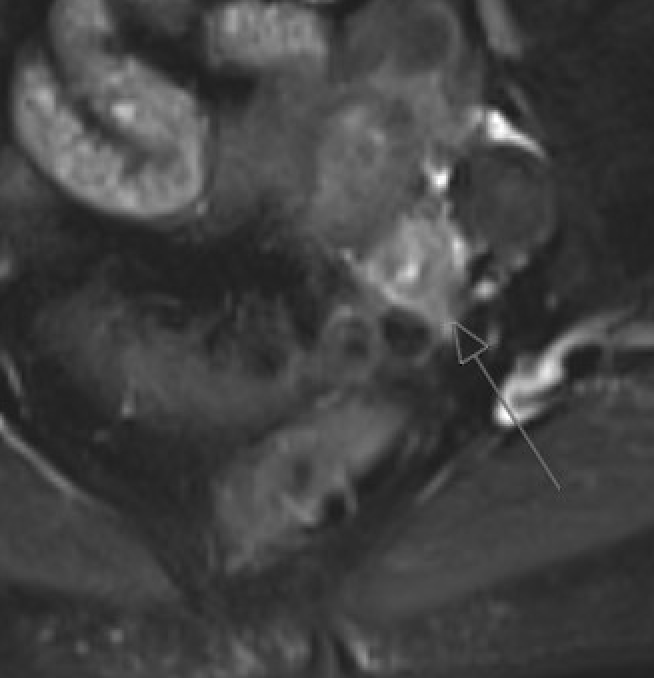

Ovarian torsion (pregnancy) Enlarged ovary with peripheral follicles and stromal edema on T2W. Pelvic ascites. Compare with contralateral ovary. Whirlpool sign of twisted pedicle

MRI showing ovarian torsion with enlarged ovary, peripheral follicles, and stromal edema on T2W

Ovarian torsion: enlarged ovary, peripheral follicles, stromal edema